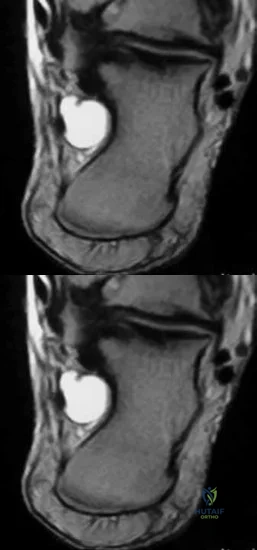

Question 23

A 25-year-old male athlete presents with deep ankle pain 6 months after an inversion injury. MRI reveals a 1.2 cm^2 osteochondral lesion of the medial talar dome with intact overlying cartilage. He has failed non-operative management. What is the most appropriate next step in treatment?

Explanation